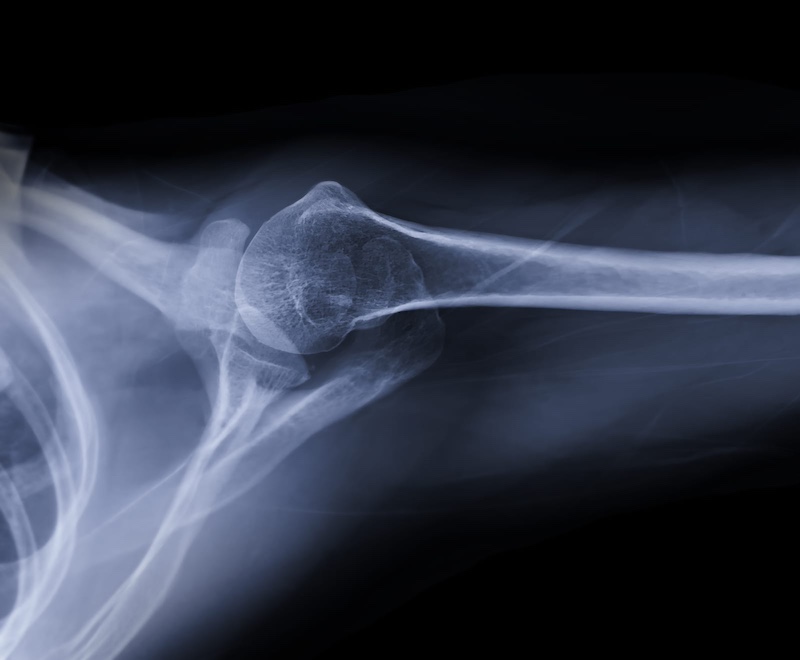

Anterior shoulder dislocations top the list of skiing shoulder injuries, representing approximately 52% of all shoulder problems seen in ski clinics. These occur when the arm forcefully extends and rotates externally during a fall, popping the humeral head out of the socket. The injury causes immediate, severe pain and visible deformity. The arm typically locks in an awkward position away from the body.

First-time dislocations often stretch or tear the labrum, a ring of cartilage that deepens the shoulder socket. This damage increases the risk of future dislocations, creating a cycle that can plague skiers for years. Younger athletes face particularly high recurrence rates without proper treatment and rehabilitation. Some dislocations also involve fractures of the glenoid rim or humeral head, complicating treatment and recovery.